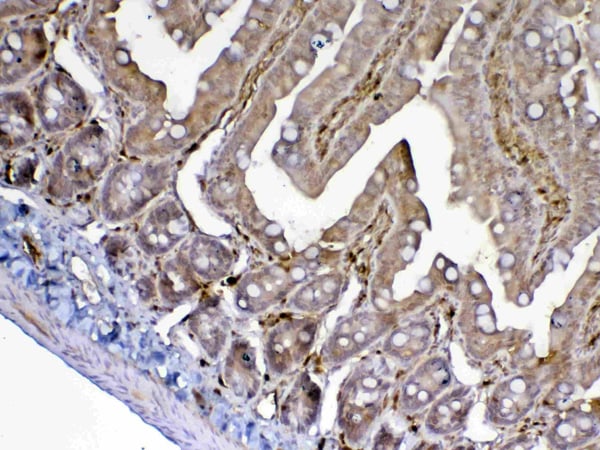

E-Cadherin/CD324, Monoclonal Antibody (Cat# AAA23896)

Does not react with Mouse and Rat. Others not known.